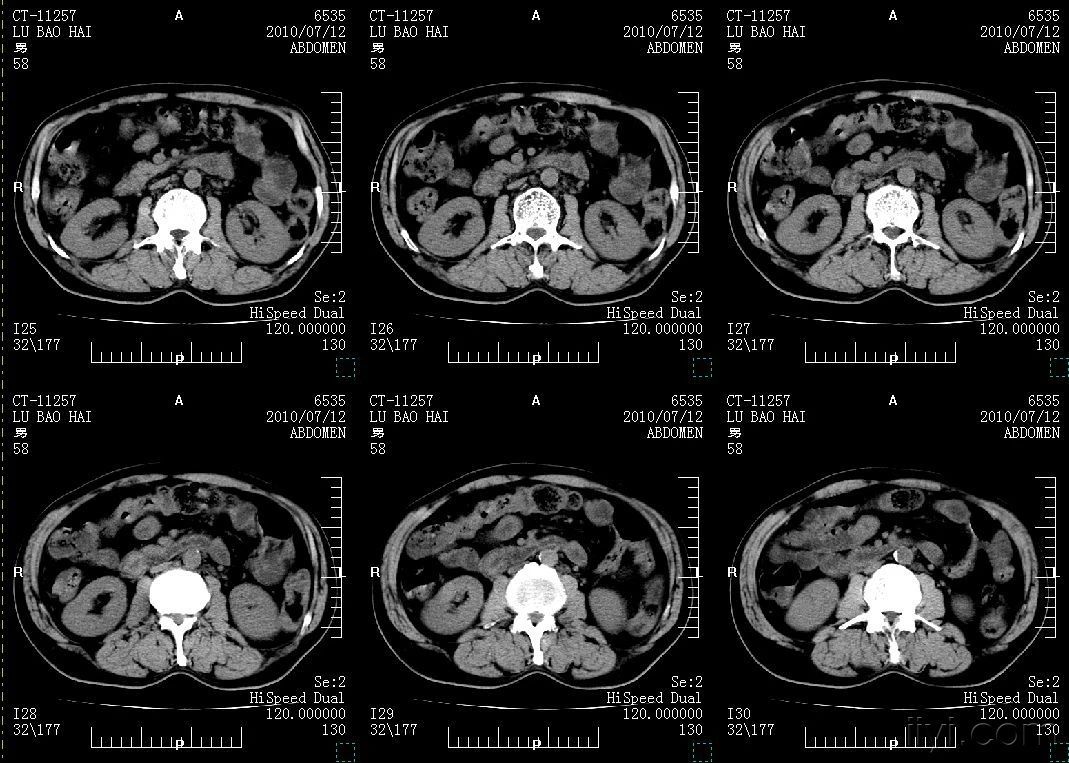

2、CT表现:

(1)平扫:肝内低密度区,轮廓清楚,密度均匀或病变区内有更低密度区,代表血栓机化或纤维分隔,少数可见到钙化;

(2)增强扫描:

①早期病变边缘显着强化呈结节状或岛屿状,密度与邻近腹主动脉相近,明显高于周围肝实质密度,持续时间超过2分钟;

②随着时间延长,增强幅度向病变中央推近,而病变的低密度区相对变小;

③延时扫描病变呈等密度或略高密度(平扫时病变内更低密度无变化)增强扫描是诊断肝海绵状血管瘤的重要方法,具有特征性表现,诊断正确率可在90%以上一般典型表现出现在动脉早期,即注药后30~60秒因此强调正确的检查技术,即快速、团状注射造影剂,快速扫描,适时延时扫描否则,因未见到特征性表现易造成误诊或漏诊。